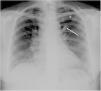

A 22-year-old woman was referred to our emergency radiology unit with sudden onset of shortness of breath and left-sided chest pain. The chest radiography revealed left hilar tubular opacite (arrow) and hyperaeration (asterisk) in the upper zone of the left lung (Fig. 1). The contrast enhanced computed tomography (CT) showed a non-contrast enhancing tubular mass that was seen extending from the left hilum, with surrounding hypoattenuation of the apicoposterior segment of the left upper lobe (asterisk), a finding indicative of hyperinflation (Fig. 2A). There was also no connection between the non-contrast tubular mass (arrows) and pulmonary artery of the apicoposterior segment in the left upper lobe (Fig. 2B–C). CT findings were also including mucocele and occlusion of the bronchus central to the mucocele. CT results (mucocele with hyperaeration of the adjacent lung parenchyma) were considered pathognomonic for bronchial atresia. Surgical treatment was no performed because the patient refused operation.